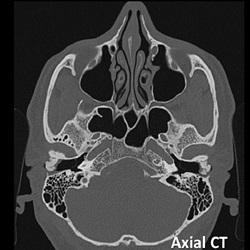

#AJNRcc >> December 23, 2024 >> What is the diagnosis for this 47 year-old man with insidious bilateral conductive hearing loss? Submit your answer at https://t.co/HMHAWnZYWF.